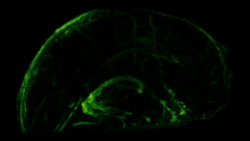

Although several studies proposed the existence of lymphatic vessels in the dura mater, the presence of the meningeal lymphatic system was accepted in 2015, when two independent studies published by Louveau et al.[1] and Aspelund et al.[2] provided convincing data using novel methods. Louveau et al. noticed an unusual alignment of immune cells along the dural sinus using a meningeal whole-mount technique. Using lymphatic endothelial cell-specific markers and electron microscopy, the authors found that the immune cells were not inside blood vessels, but rather were organized inside lymphatic vessels within the meninges, a system of membranes that envelop the brain and spinal cord.[1]

In transgenic mice containing Prox1-GFP or Vegfr3-LacZ reporter genes, the lymphatic vessels may be visualized by fluorescent microscopy or after X-gal staining, respectively.[2]

The meningeal lymphatic system is composed of a network of vessels along the dural sinus in the dura which express lymphatic endothelial cell marker proteins, including PROX1, LYVE1, and PDPN. The vessels extend along the length of both the superior sagittal and transverse sinuses and directly connects to the deep cervical lymph nodes.[1] These meningeal lymphatic vessels drain down and exit the skull along the dural venous sinuses and meningeal arteries. Meningeal lymphatic vessels also drain out of the skull alongside cranial nerves and through the cribriform plate. Molecular profiling indicates that the vessels are conventional lymphatic vessels: they express high levels of PROX1, LYVE1, PDPN and VEGFR3, but low levels of PECAM1. Meningeal lymphatic vessels absorb cerebrospinal fluid and drain into the deep cervical lymph nodes.[2]

Several unique attributes differentiate meningeal lymphatic vessels from lymphatic vessels in peripheral organs. Compared to peripheral lymphatic vessels, the meningeal lymphatic network is markedly less complex, with far less tissue coverage and lymphatic branching. Furthermore, meningeal lymphatic vessels are generally smaller than those in the periphery and display a structural homogeneity along the dural sinuses, remaining thinner and mostly unbranched along the superior sagittal sinus while growing larger and more branched along the transverse sinuses.[1] The meningeal lymphatic vessels are also unique for their scarcity of valves, which prevent back-flow of lymph. While the vessels in the superior parts of the skull were mostly devoid of valves, the larger lymphatic vessels of the basal parts only contain scattered valves.[2]